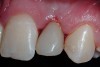

The 3-month postoperative views can be seen in Figure 18 through Figure 20. Note the excellent soft tissue emergence profiles obtained from the properly contoured provisional restorations. After removal of the provisional restorations, further inspection of the contoured emergence profile obtained has been accomplished (Figure 21 and Figure 22). Before impression techniques, transfer copings were seated over the abutment portion of the one-piece implant (Figure 23). A full-arch impression was then taken using medium-body impression material (Take 1 Advanced, Kerr Corporation, Orange, CA) and a regular-body wash material (Take 1 Advanced) to pick up the detail of the emergence profile and impression coping (Figure 24 through Figure 26). After allowing the impression material to set, the impression is then removed from the mouth and inspected (Figure 27). The Take 1 Advanced Medium body has a more rigid set than most other medium materials, so when the coping is placed back in the impression, the possibility of movement during casting is reduced. Please note how the emergence profile obtained has been registered in the impression, and can easily be transferred to the laboratory technician. Laboratory analogues are then placed into the impression coping and forwarded to the laboratory technician for pouring of the casts and final fabrication of the esthetic implant restorations (Figure 28).